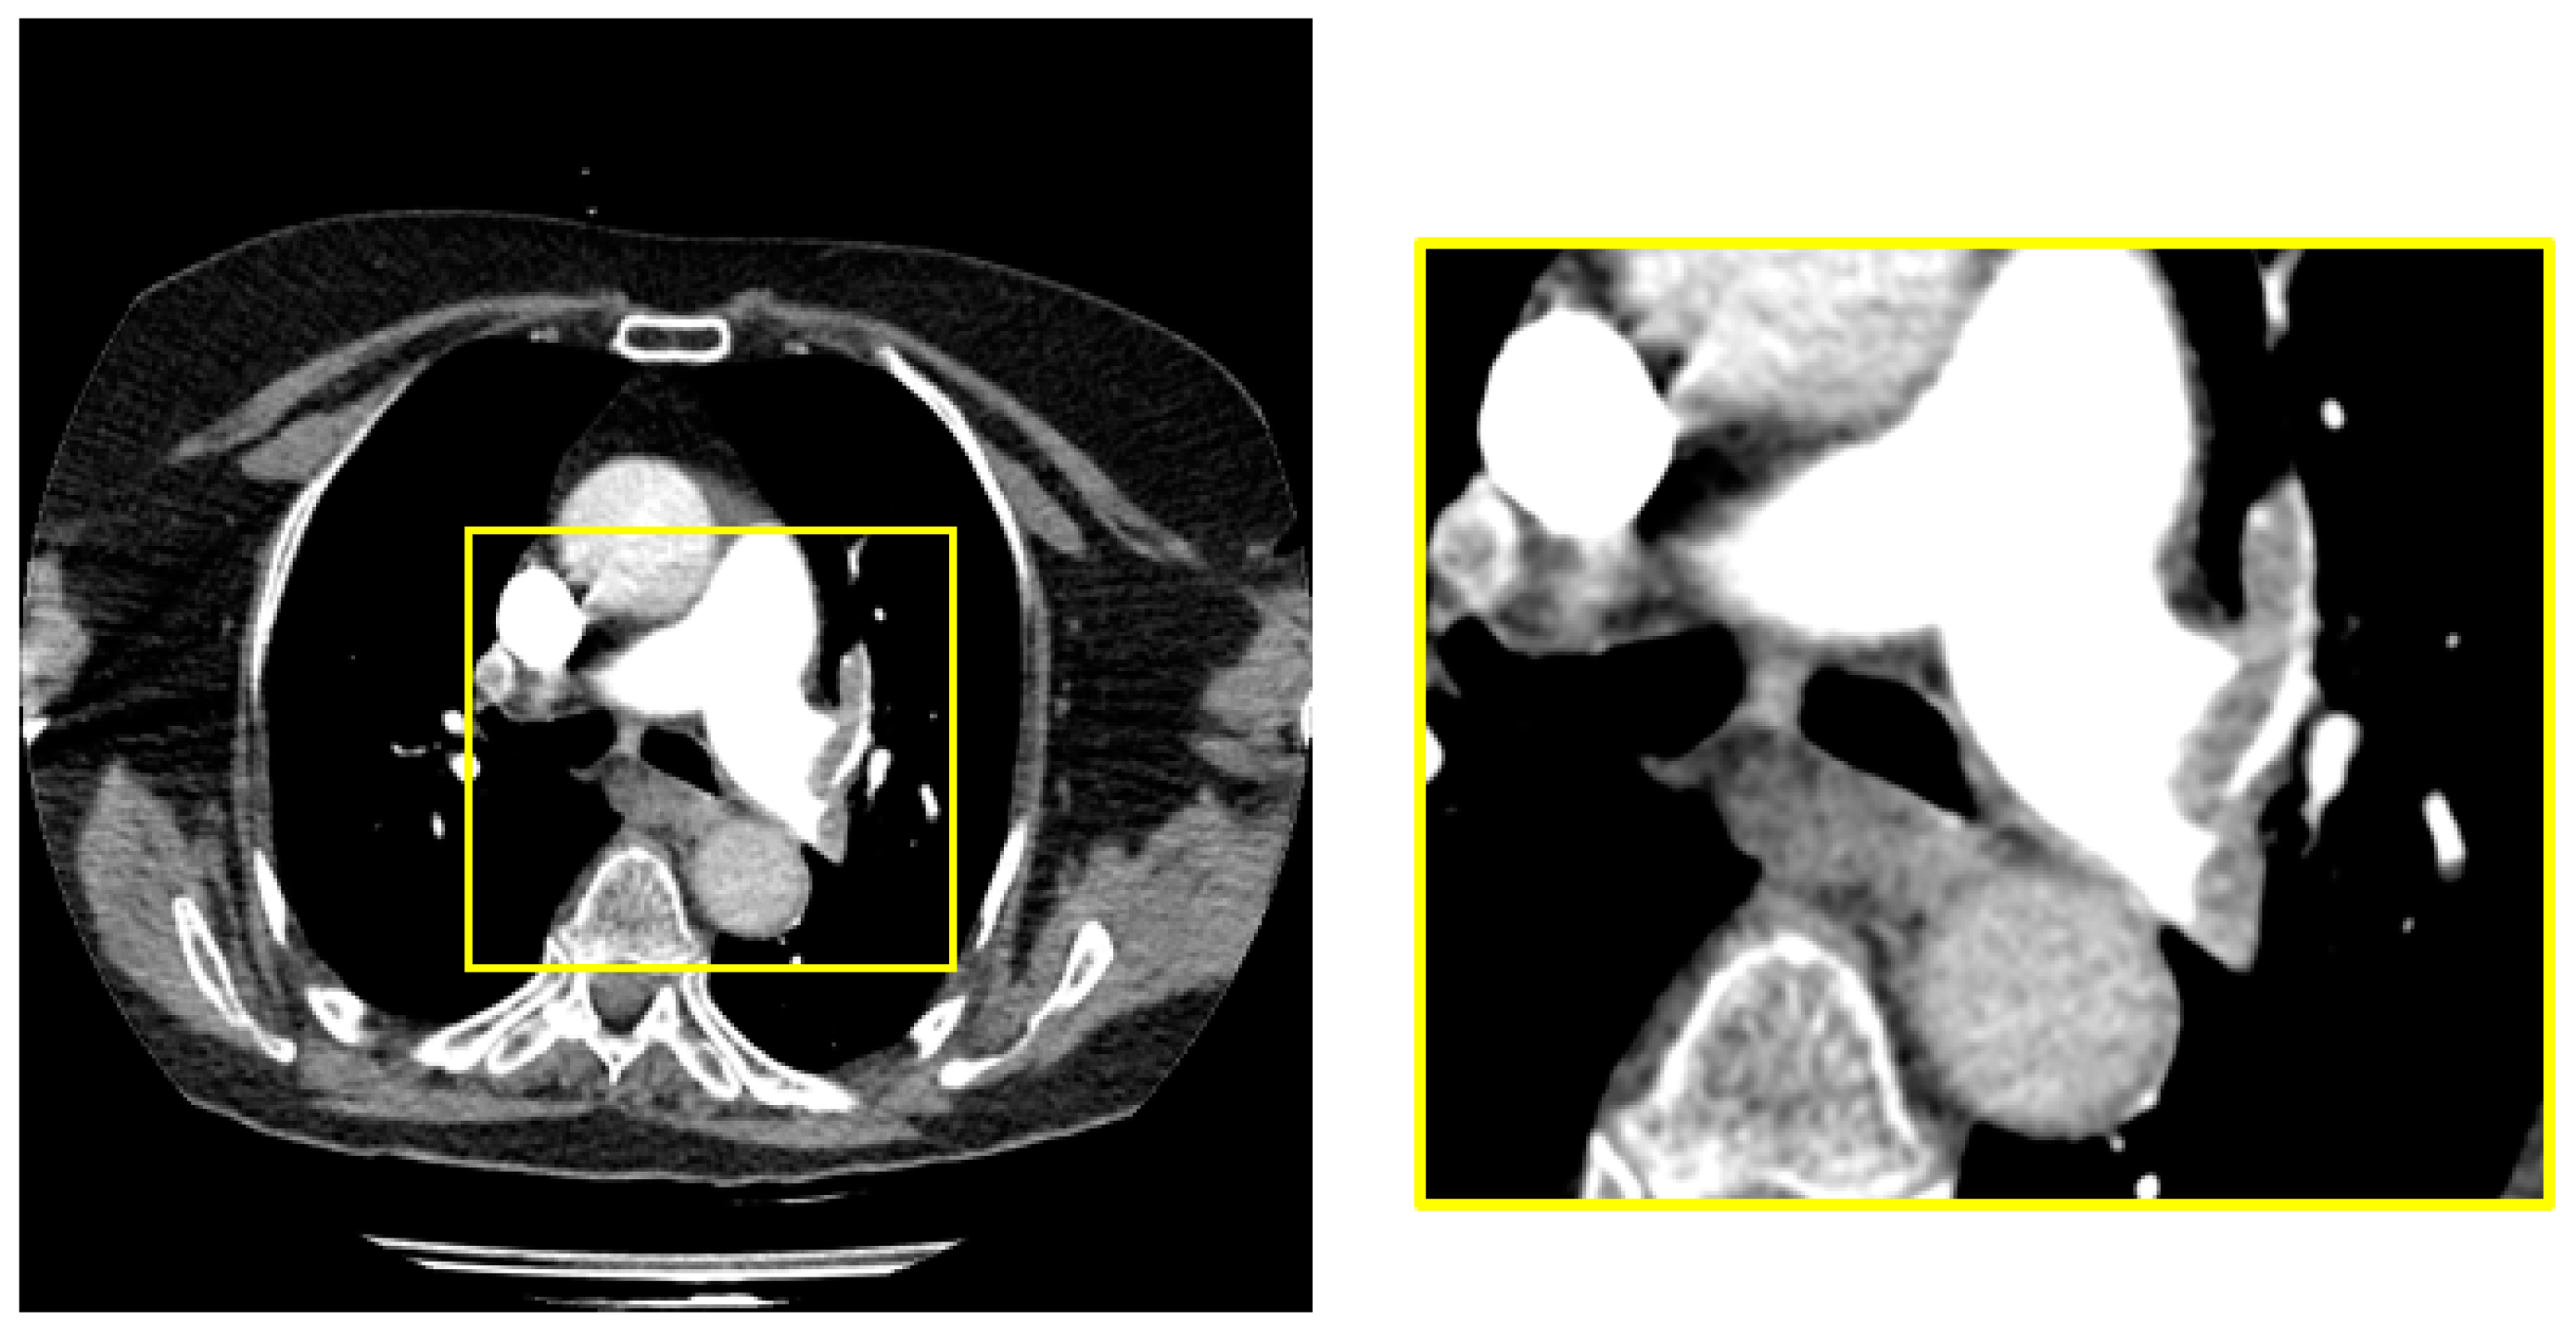

2.2. Pre-Processing